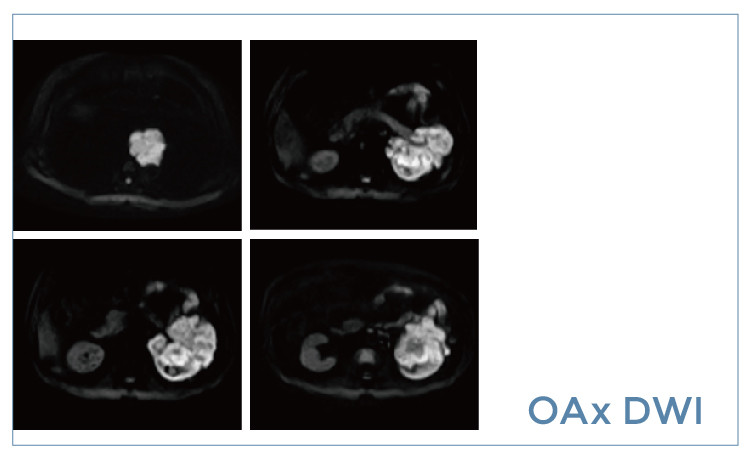

【朗润影像档案】磁共振影像病例分享(编号20190426)